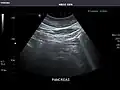

Ultrasound can be used for additional anatomical information for patients with an abnormal kidney function or pancreatic enzymes (pancreatic amylase and pancreatic lipase).

Pancreas: Visualized portions unremarkable.

Pancreas -